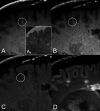

Background and purpose: We hypothesized that 3D T1-TSE "black-blood" images may carry an increased risk of contrast-enhancing lesion misdiagnosis in patients with MS because of the misinterpretation of intraparenchymal vein enhancement. Thus, the occurrence of true-positive and false-positive findings was compared between standard MPRAGE and volumetric interpolated brain examination techniques.

Results: The intraparenchymal vein contrast-to-noise ratio was higher in SPACE than in MPRAGE and volumetric interpolated brain examination images (P < .001, both). There were 66 true-positives and 74 false-positives overall. SPACE detected more true-positive and false-positive results (P range < .001-.07) but did not increase the patient's true-positive likelihood (OR = 1 1.29, P = .478-1). However, the false-positive likelihood was increased (OR = 3.03-3.55, P = .008-.027). Venous-origin false-positives (n = 59) with contrast-to-noise ratio and morphology features similar to small-sized (≤14 mm3 P = .544) true-positives occurred more frequently in SPACE images (P < .001).

Conclusions: Small intraparenchymal veins may confound the diagnosis of enhancing lesions on postgadolinium black-blood SPACE images.